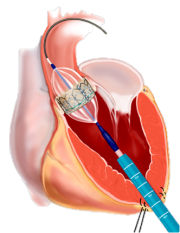

This procedure involves the replacement of the aortic valve to about 70% of the aortic valve via the artery in the groin (transfemoral), about 30% via a small cut on the left side of the thorax through the apex of the heart (transapical). Alternatively, access via a clavicle artery or directly over the aorta can be selected. In all cases, the constricted heart is first distended with a constricted aortic valve (balloon valvuloplasty). Subsequently, a vascular prosthesis with integrated biological heart valve is introduced via a catheter and unfolded at the level of the diseased aortic valve (implantation). The flap anchors itself with a so-called stent in the correct position. This technique is also suitable for new valve implantation in degenerated bioprostheses (valve in valve technique). However, the process has a disadvantage: the calcified heart valves remain in the heart and the lime can dissolve over the years.

Technique of Percutaneous Aortic Valve Implantation: Left Transapical, Right Transfemoral